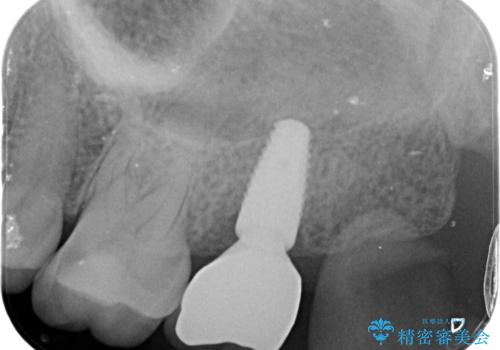

歯の抜去後、しっかりと咬合機能を回復するためインプラントを用いた治療を行っていきます。

- 50.4万円(インプラント・チタンカスタムアバットメント・ジルコニアクラウン・仮歯)費用は治療当時の料金となります

歯の破折で抜歯を余儀なくされ、ショックが大きかったですが、しっかりとインプラントで咬合機能が回復することができ、喜んでいただくことができました。